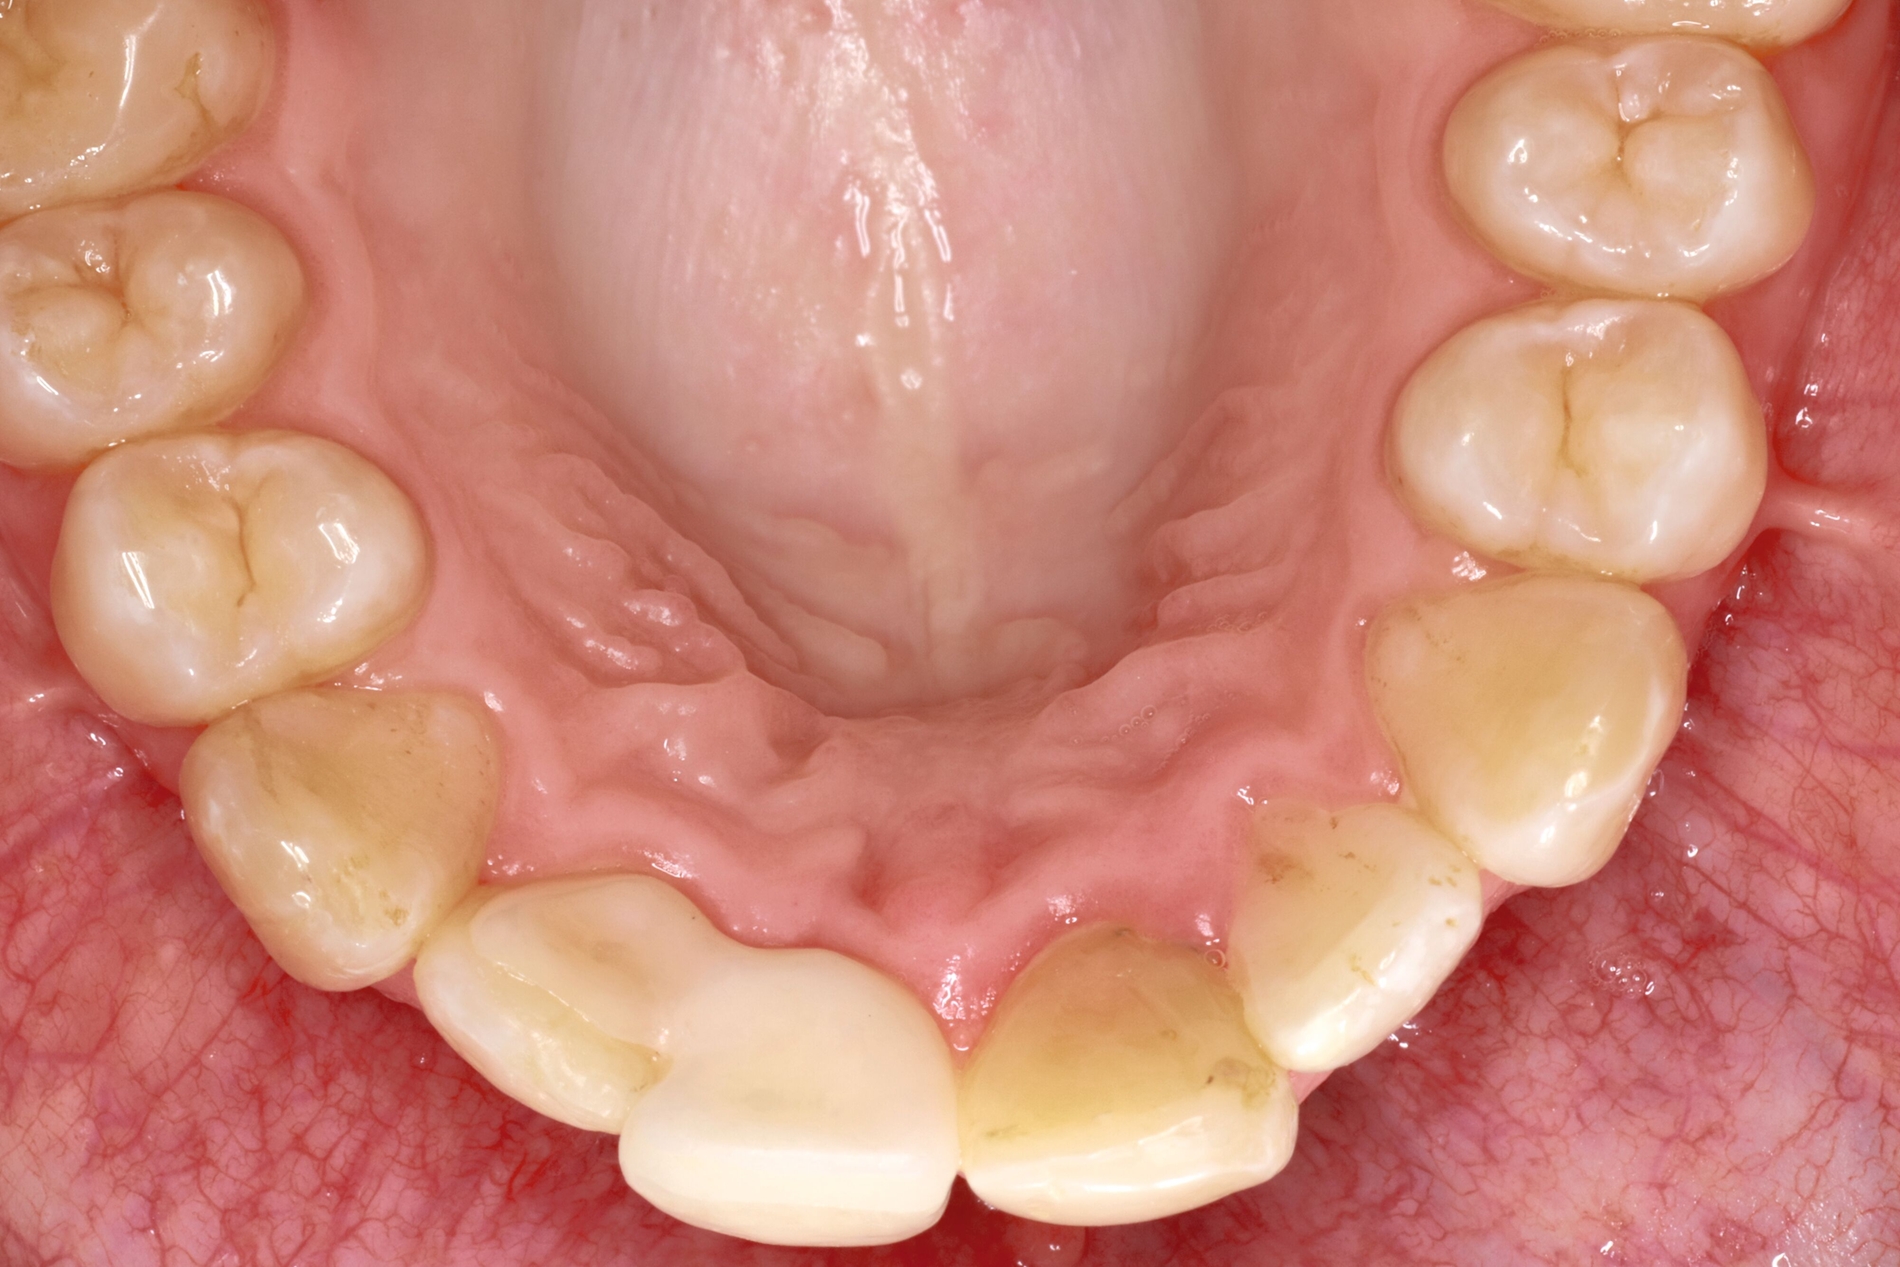

Die adhäsive Wiederbefestigung mitgebrachter Kronenfragmente bietet sich als einfache und konservative Methode zur Wiederherstellung von Funktion und Ästhetik an (Abbildung 1). Wenn das Fragment nach dem Unfall unter feuchten Bedingungen gelagert wurde, wird die Wiederbefestigung idealerweise sofort während der Notfallbehandlung durchgeführt. Wurde das Fragment jedoch durch eine längere Trockenlagerung dehydriert, sind sowohl das ästhetische Ergebnis als auch die Komposithaftung kompromittiert. In solchen Fällen wird eine Lagerung in physiologischer Kochsalzlösung oder in Wasser für einen Tag empfohlen, um eine Rehydrierung des Fragments zu ermöglichen [Farik et al., 1999], während das Dentin in der Zwischenzeit mit einem leicht entfernbaren temporären Material bedeckt ist (zum Beispiel Kalziumhydroxid-Zement). Die Rehydrierungszeit kann durch eine feuchte Lagerung des Fragments in einem sauberen Drucktopf auf 30 bis 60 Minuten verkürzt werden.